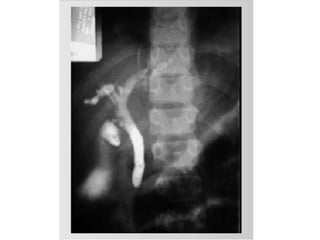

Colangiografía

Colangiografia.Definicion y utilidades

Dra. Claudia Amarilla